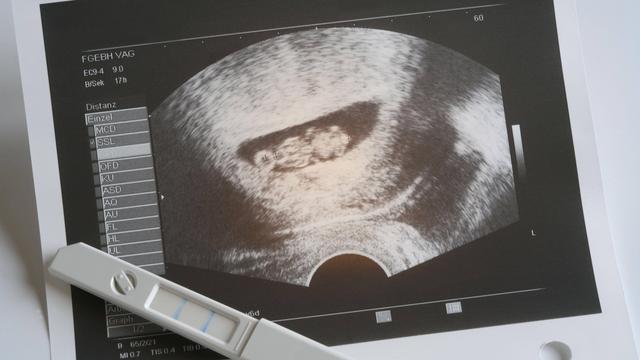

Im ersten Trimester der Schwangerschaft, genauer gesagt ab der 5. Woche, beginnt das Herz des Embryos zu schlagen. Dieser Herzschlag kann bereits ab der 6. Woche im Ultraschall sichtbar gemacht werden. Der Arzt kann die Herztöne des Babys hören und auf dem Bildschirm des Ultraschallgeräts sehen. Der Herzschlag ist ein wichtiger Meilenstein in der Entwicklung des Embryos und ein Zeichen dafür, dass alles gut verläuft. Es ist ein bewegender Moment für die werdenden Eltern, den Herzschlag ihres Kindes zum ersten Mal zu hören oder zu sehen.

Der Herzschlag im Ultraschall wird als Hinweis auf eine intakte Schwangerschaft betrachtet und gibt den Ärzten und Eltern Sicherheit über das Wohlbefinden des Babys. Es ist wichtig zu beachten, dass der Zeitpunkt des ersten Nachweises des Herzschlags im Ultraschall von verschiedenen Faktoren abhängen kann, wie zum Beispiel von der Position des Embryos und der Qualität des verwendeten Ultraschallgeräts.

Der Herzschlag des Fetus kann ab der 5. Schwangerschaftswoche (SSW) im Ultraschall festgestellt werden. In dieser Zeit beginnt das Herz zu schlagen und der Herzschlag ist bereits ab der 6. Woche auf dem Ultraschall sichtbar. Der Herzschlag wird als ein wichtiger Meilenstein in der frühen Schwangerschaft angesehen, da er darauf hinweist, dass die Entwicklung des Embryos gut verläuft.

– Der Herzschlag kann mit Hilfe eines vaginalen Ultraschalls oder eines Bauchultraschalls festgestellt werden.